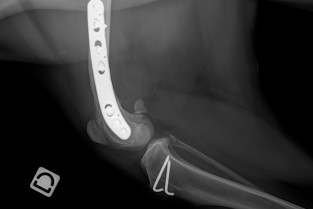

L'objectif pédagogique de ce cours avancé est de renforcer les connaissances en pathologie ostéo-articulaire chez le chien et le chat. Des mises au point concernant les connaissances les plus récentes seront réalisées cette année sur les affections du grasset. L'accent sera toujours mis sur le côté pratique et visuel. Un temps important sera consacré à la discussion après chaque exposé. Le succès des "cas cliniques interactifs" a conduit à leur accorder une part importante dans le programme de ce cours.

- connaitre les principales affections ostéo-articulaires du grasset;

- savoir proposer une attitude thérapeutique adaptée pour chacuned'entre elles.